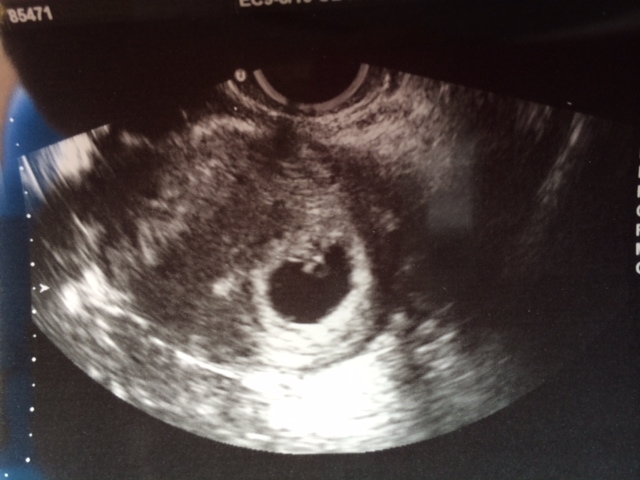

I went yesterday for my early ultrasound - 6 weeks 1 day and the baby was attached in the middle at the top with the yolk sac directly beneath it. The pic with the yolk sac is hard to tell because everything was so squished but it really was not swayed one side or the other. does anyone have any experience with Ramzi when the baby implants smack dab in the center? My first two boys were clearly in the right bottom corner, so this is throwing me off! And of course I am dying to know and willing to study every little detail!!Attachment 15570Attachment 15571